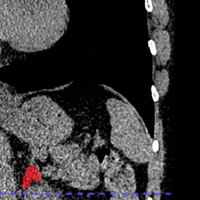

The state-of-the-art technology was used to assess routine chest scans.

Using a deep learning AI model , American researchers identified the first-of-its-kind biomarker of chronic stress detectable through routine imaging.